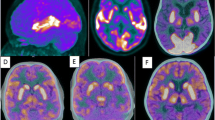

Subject 6: A 13-year old girl admitted for hallucinations and delirium followed by decreased level of consciousness, seizures, dystonia and fever. Initial working diagnosis of herpes encephalitis. CSF analysis demonstrated normal protein and glucose levels, negative for viral and bacterial infection but positive for anti-NMDAr antibodies. Ultrasound of the abdomen showed an ovarian lesion which was subsequently removed and for which the pathology was in keeping with teratoma. As the patient was not improving, despite immuno-modulatory treatment and surgery and in the presence of normal brain CT and MRI, FDG PET was ordered for reevaluation. Qualitative brain PET shows diffuse symmetrical hypometabolism, more marked in the posterior temporal, parietal and occipital lobes, with increased activity in the basal ganglia. NeuroQ™ analysis demonstrates hypermetabolism in the basal ganglia and multiple regions of relative hyper and hypometabolism, the latter predominantly in the posterior regions. NeuroQ™ analysis results overlying the adult template. Red: RRBM > upper limit of 95% prediction interval; blue: RRBM < lower limit of 95% prediction interval; green: RRBM within the 95% prediction interval